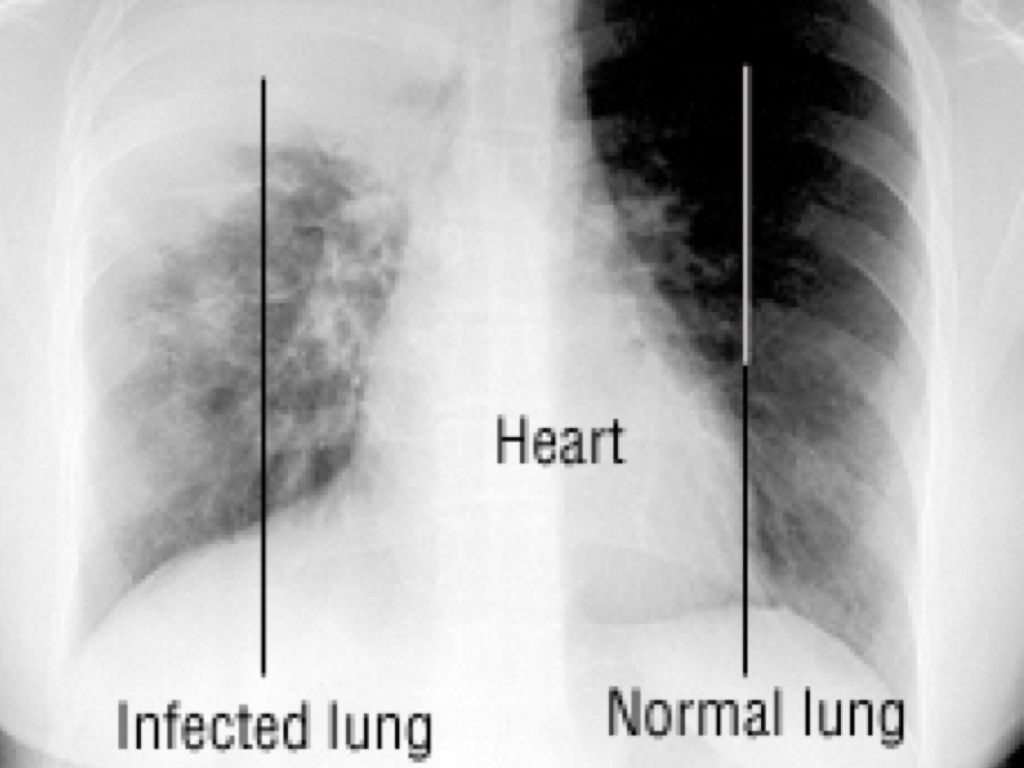

LUNG CANCER

• Lung cancer is one of the most common and serious types of cancer. Around 44,500 people are diagnosed with the condition every year in the UK.

• There are usually no signs or symptoms in the early stages of lung cancer, but many people with the condition eventually develop symptoms including: a persistent cough coughing up blood persistent breathlessness unexplained tiredness and weight loss an ache or pain when breathing or coughing

PNEUMONIA

• 1 in every 100 UK adults develop pneumonia each year?

• More than 50,000 UK adults die of pneumonia each year4. In the UK, it is one of the most common causes of death due to infection in men and women

• If you have a heart condition and have pneumonia, you are four-times more likely to have a heart attack or stroke

• Pneumonia is more common and can be more serious in people that smoke.